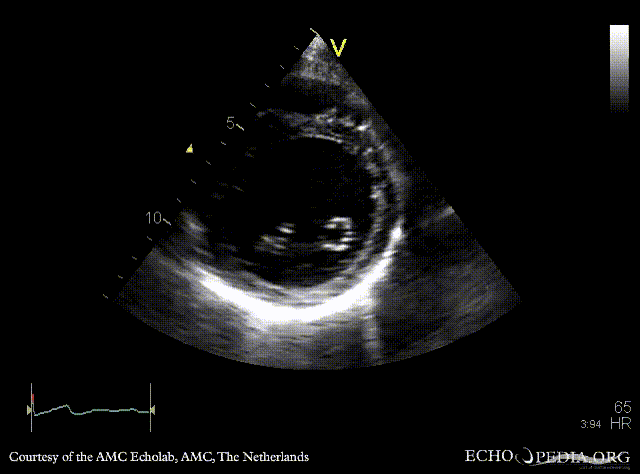

Dilated cardiomyopathy

A2CH A3CH: Color Doppler, moderate mitral regurgitation